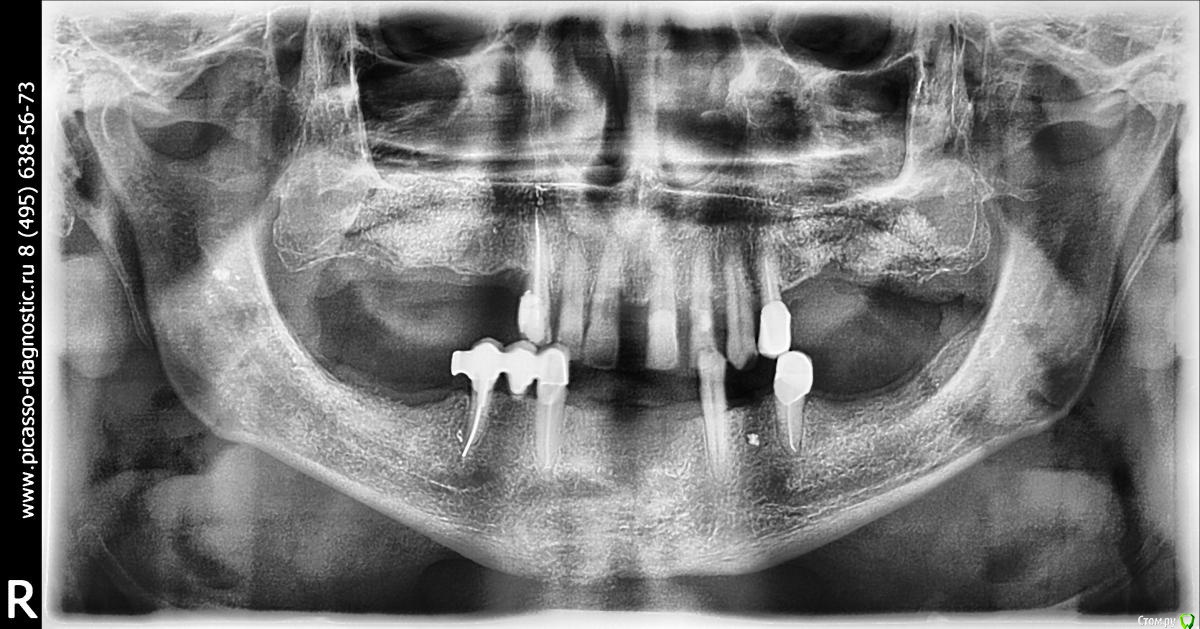

Larnary Опубликовано 1 февраля, 2015 Поделиться Опубликовано 1 февраля, 2015 Всем добрый вечер! ко мне обратилась подруга за помощью. ее отца долго мучали в какой-то супер дорогой клинике,развели на сотни тысяч,а результата нет. мне нужно составить план грамотного лечения данной ситуации. пациент обеспеченный и может себе позволить современное лечение. в данной клинике ему предлагали покрывные протезы на имплантах на обе челюсти. Жду мнения форума,кто,что может предложить. Зараннее спасибо Ссылка на комментарий

DR.P Опубликовано 1 февраля, 2015 Поделиться Опубликовано 1 февраля, 2015 Низ либо все удалять и делать условносъемный на балке, либо удалять 4.5 и делать бюгель на телескопах с шариковым аттачментом или фрикционным штифтом. Верх мк мост учитывая состояние нижней челюсти - мост. Жевательную группу либо имплантаты или бюгель Ссылка на комментарий

SDC Опубликовано 1 февраля, 2015 Поделиться Опубликовано 1 февраля, 2015 Тщательно соберите анамнез и что именно и на какие сотни было сделано.Я вижу, что графта насыпано на приличную сумму. А то подруга подругой, а всякое бывает Ссылка на комментарий

Larnary Опубликовано 1 февраля, 2015 Автор Поделиться Опубликовано 1 февраля, 2015 (изменено) графта насыпано на полляма деревянных. с учетом суммы и статуса линики премиум класса,то предполагаю,что био осс. но уточню.и что за клиника-тоже спрошу. Если делать верх импланты, то хватает ли графта слева? Изменено 1 февраля, 2015 пользователем Larnary Ссылка на комментарий

колесников Опубликовано 1 февраля, 2015 Поделиться Опубликовано 1 февраля, 2015 для начала : что хочет пациент? съёмный,несъёмный,что по эстетике предъявляет? носил ли съмные до того? что с внчс? готов ли растаться с оставшимися зубами? когда сделана пластика? он вкурсе что слева она не удалась? теперь к вам. как вы привыкли работать,классика или немедленая нагрузка? знакомы с ,,всё на 4ёх,, или ,,всё на 6ти,,? пластика прикреплёной слизистой или ,,розовая десна,, на протезе? с какими системами предпочитаете работать?исходя из вариантов ответов на эти вопросы можно предлагать варианты плана лечения. на мой взгляд всё удаляется и имплантируется. но этапность , количество имплантов и конечный вид конструкции пока не понятен. 1 Ссылка на комментарий

Larnary Опубликовано 1 февраля, 2015 Автор Поделиться Опубликовано 1 февраля, 2015 (изменено) значит отвечу по пунктам. к съемному пациент готов,тк его ориентировали к съемнику на имплантах. съемник носил-видно по замку на премоляре низ справа. срасстаться с зубами готов,но скрипя зубами.работать привык по классике. съемников на имплантах в моей практике было мало. имплантолог у меня опытный,пластику делает. с розовой десной на протезе знаком конечно. системы у нас в клинике Semados и Mis Изменено 1 февраля, 2015 пользователем Larnary Ссылка на комментарий

DoctorT Опубликовано 1 февраля, 2015 Поделиться Опубликовано 1 февраля, 2015 (изменено) Если без имплантов, то я бы посоветовал: н/ч удаление 35,45. На 3.3 и 4.3 телескопические коронки сверху псп с фиксацией на телескопах. Вид фотографии с множеством шариков на одиночных коронках меня просто поверг в шок (это наверное новый способ удаления). В/ч реальная проблема в виде диастемы, закрывая которую, получим весьма широкие зубы 1.1 2.1. Можно конечно с совершить попытку изготовления мостовидного протеза на 1.3 1.2 1.1 2.1 2.2 2.3 + бюгель с фиксацией на фрезеровках ( можно добавить по пару замочков на 1.3 и 2.3). В идеале верх весь на выход и все на 4 сделать.)) пока писал, уже новый ответ)) Изменено 1 февраля, 2015 пользователем DoctorT Ссылка на комментарий

колесников Опубликовано 1 февраля, 2015 Поделиться Опубликовано 1 февраля, 2015 (изменено) значит отвечу по пунктам. к съемному пациент готов,тк его ориентировали к съемнику на имплантах. съемник носил-видно по замку на премоляре низ справа. срасстаться с зубами готов,но скрипя зубами.работать привык по классике. съемников на имплантах в моей практике было мало. имплантолог у меня опытный,пластику делает. с розовой десной на протезе знаком конечно. системы у нас в клинике Semados и Misкое что прояснилось. я думаю внизу съёмник стоит оставить. пациент привык ,а у нас тут приличное межальвеолярное . делать ли бюгель или съёмный на имплатах-это детали. внимание на верх. фронт хоть и крепкий но имеет место клиническое выдвижение и приличные диастемы. их либо собирать ортодонтически либо распрощаться с ними. меня смущает область синуслифтинга справа. по виду это интегрированый био-ос. это самый плохой вариант интегрированого материала. примерно 1го типа и абсолютно не васкуляризированый. имел неприятный опыт работы с такой костью. интеграции имплантата не произойдёт. что делать? можно попробовать сформировать ложе под имплант и оставить на месяц-полтора,а после установить имплант. либо обойти эту зону. слева ещё хуже-там прорастание эпителия между гранул материала. опять же либо не трогать либо повторная пластика.... короче надо прикинуть на артикуляторе,покрутиь кт. подумать ,посчитать. но всегда остаётся 4 импланта во фронте и балка Изменено 1 февраля, 2015 пользователем колесников 1 Ссылка на комментарий